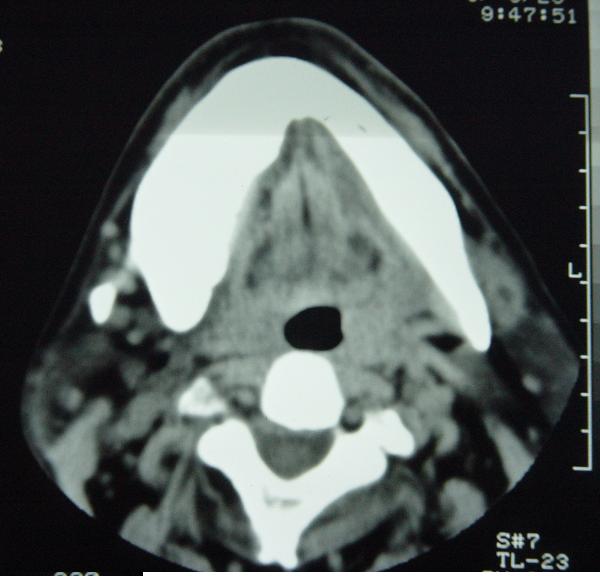

标题: CT12465:下颌骨肿瘤,请会诊 [打印本页]

标题: CT12465:下颌骨肿瘤,请会诊

发现下颌骨肿瘤近30年.逐渐增大.

造釉细胞瘤,没有特征性;半月切迹?骨间隔?多房性骨密度减低区,大小不等。鉴别;动脉瘤样骨囊肿,骨软骨瘤。本人,更倾向于---骨软骨瘤。